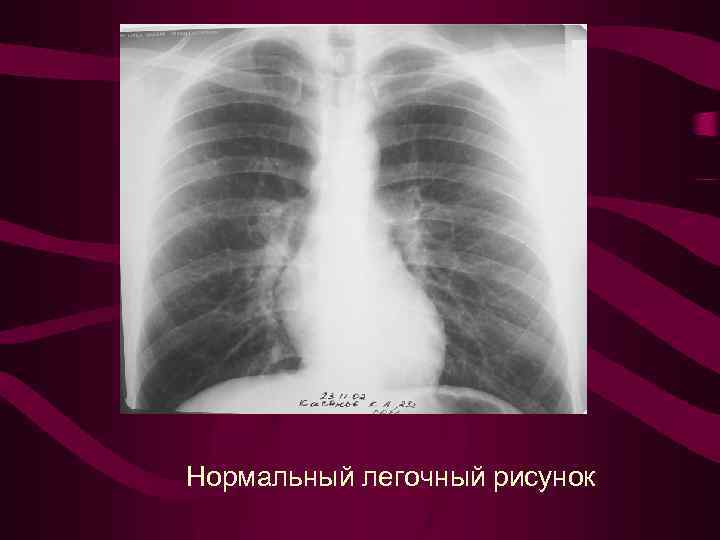

Нормальный легочный рисунок

Нормальный легочный рисунок

Рентгенанатомия малого круга кровообращения Р-изображение нормального легочного рисунка образовано за счет сосудов, в основном артерий Диаметр сосудов пропорционален интенсивности кровотока в них и в норме уменьшается от центра к перифирии

Рентгенанатомия малого круга кровообращения Р-изображение нормального легочного рисунка образовано за счет сосудов, в основном артерий Диаметр сосудов пропорционален интенсивности кровотока в них и в норме уменьшается от центра к перифирии

Классификация рентгенологических симптомов перераспределения легочного кровотока при левожелудочковой недостаточности. Степень и синдромы рентгенологических изменений в малом круге Рентгенсемиотика перераспределения легочного кровотока 0–изменения отсутствуют Нормальный легочный рисунок 1 -верхнедолевой венозный застой (инверсия легочного кровотока) Усилен легочный рисунок в верхних долях, укрупнен колибр верхнедолевых вен. Корни легких обычной величины, но может отмечаться его незначительное расширение и увеличение колибра ортогональных теней сосудов в центральных отделах корня. Изменения соответствуют среднему давлению в левом предсердии от 10 до 15 мм рт. ст. 2 -диффузный застой венозный Усилен венозный легочный рисунок во всех отделах легких до перифирии. Увеличено количество сосудистых теней на единицу площади легочного поля. Корни легких расширены структура их не дифференцируется. Отмечается нерезкость контуров корня и сосудов. Изменения соответствуют среднему давлению в левом предсердии от 15 до 25 мм рт. ст. 3 - интерстициальный отек легких На фоне диффузного венозного застоя выявляются признаки нарушения лимфооттока из легких. Прозрачность легочных полей понижена. Легочный рисунок усилен, полиморфный, наблюдается ячеистая его деформация с нечеткостью контуров сосудов и бронхов. Выявляются линии Керли, плевральные линии, небольшое количество выпота в плевральную полость и междолевые щели, чаще справа. Изменения соответствуют среднему давлению в левом предсердии от 25 до 35 мм рт. ст. 4 - альвеолярный отек легких На фоне венозного застоя с признаками интерстициального отека определяются множетсвенные сливающиеся, разной величины очаговые тени в легких за счет скопления эксудата в альвеолах. Очаговость имеет неравномерную интенсивность и нечеткие очертания, может быть симметричной, двухсторонней, но может быть и односторонней. Нередко выпот в плевральных полостях. Изменения соответствуют среднему давлению в левом предсердии свыше 35 мм рт. ст. 5– венозный застой + вторичная легочная артериальная гипертензия (смешанный тип легочной гипертензии) Признаки венозного застоя в легких (2 -я или 3 -я степень изменений) сочетаются с выраженным увеличение колибра корней, напряженной их пульсацией. Увеличена 2 -я дуга по левому контуру сердечно-сосудистой тени (ствол легочной артерии). Отмечается увеличение коэффициента Мура. Признаки артериальной легочной гипертензии выражены больше, чем изменения в венозном русле.

Классификация рентгенологических симптомов перераспределения легочного кровотока при левожелудочковой недостаточности. Степень и синдромы рентгенологических изменений в малом круге Рентгенсемиотика перераспределения легочного кровотока 0–изменения отсутствуют Нормальный легочный рисунок 1 -верхнедолевой венозный застой (инверсия легочного кровотока) Усилен легочный рисунок в верхних долях, укрупнен колибр верхнедолевых вен. Корни легких обычной величины, но может отмечаться его незначительное расширение и увеличение колибра ортогональных теней сосудов в центральных отделах корня. Изменения соответствуют среднему давлению в левом предсердии от 10 до 15 мм рт. ст. 2 -диффузный застой венозный Усилен венозный легочный рисунок во всех отделах легких до перифирии. Увеличено количество сосудистых теней на единицу площади легочного поля. Корни легких расширены структура их не дифференцируется. Отмечается нерезкость контуров корня и сосудов. Изменения соответствуют среднему давлению в левом предсердии от 15 до 25 мм рт. ст. 3 - интерстициальный отек легких На фоне диффузного венозного застоя выявляются признаки нарушения лимфооттока из легких. Прозрачность легочных полей понижена. Легочный рисунок усилен, полиморфный, наблюдается ячеистая его деформация с нечеткостью контуров сосудов и бронхов. Выявляются линии Керли, плевральные линии, небольшое количество выпота в плевральную полость и междолевые щели, чаще справа. Изменения соответствуют среднему давлению в левом предсердии от 25 до 35 мм рт. ст. 4 - альвеолярный отек легких На фоне венозного застоя с признаками интерстициального отека определяются множетсвенные сливающиеся, разной величины очаговые тени в легких за счет скопления эксудата в альвеолах. Очаговость имеет неравномерную интенсивность и нечеткие очертания, может быть симметричной, двухсторонней, но может быть и односторонней. Нередко выпот в плевральных полостях. Изменения соответствуют среднему давлению в левом предсердии свыше 35 мм рт. ст. 5– венозный застой + вторичная легочная артериальная гипертензия (смешанный тип легочной гипертензии) Признаки венозного застоя в легких (2 -я или 3 -я степень изменений) сочетаются с выраженным увеличение колибра корней, напряженной их пульсацией. Увеличена 2 -я дуга по левому контуру сердечно-сосудистой тени (ствол легочной артерии). Отмечается увеличение коэффициента Мура. Признаки артериальной легочной гипертензии выражены больше, чем изменения в венозном русле.